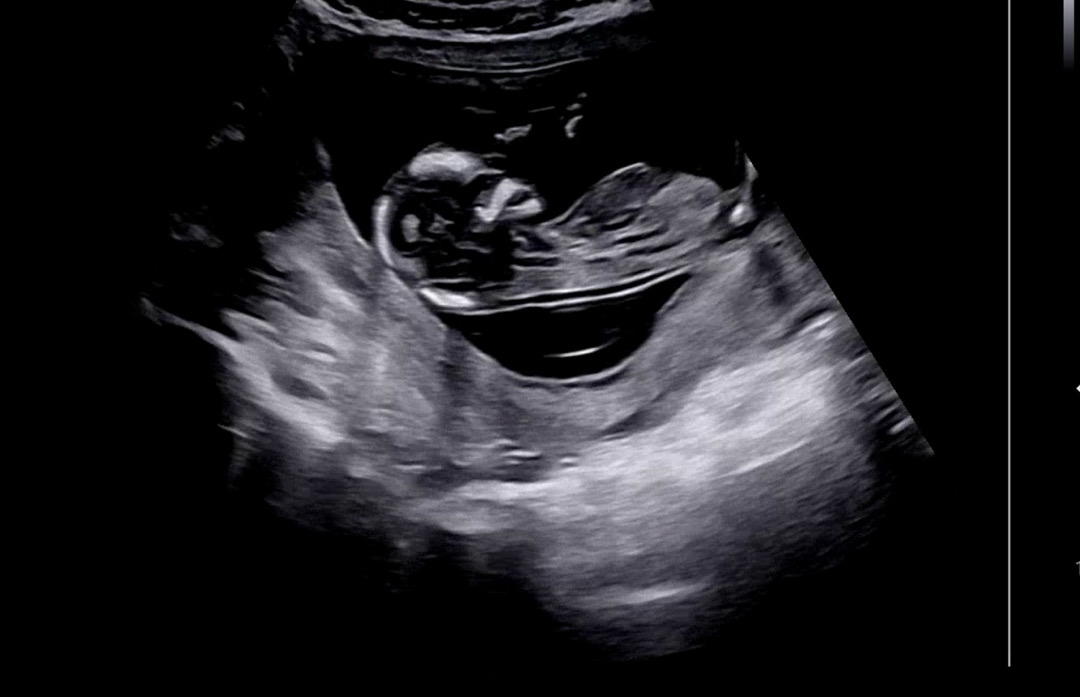

혹시 각도 보이시나요.?

저는 봐도 봐도 잘 모르겠는데 ㅠㅠ 아들이다 생각하고는 있는데 어떻게 보시나요!

딸에 한표요~

딸일거같은데 애매.....